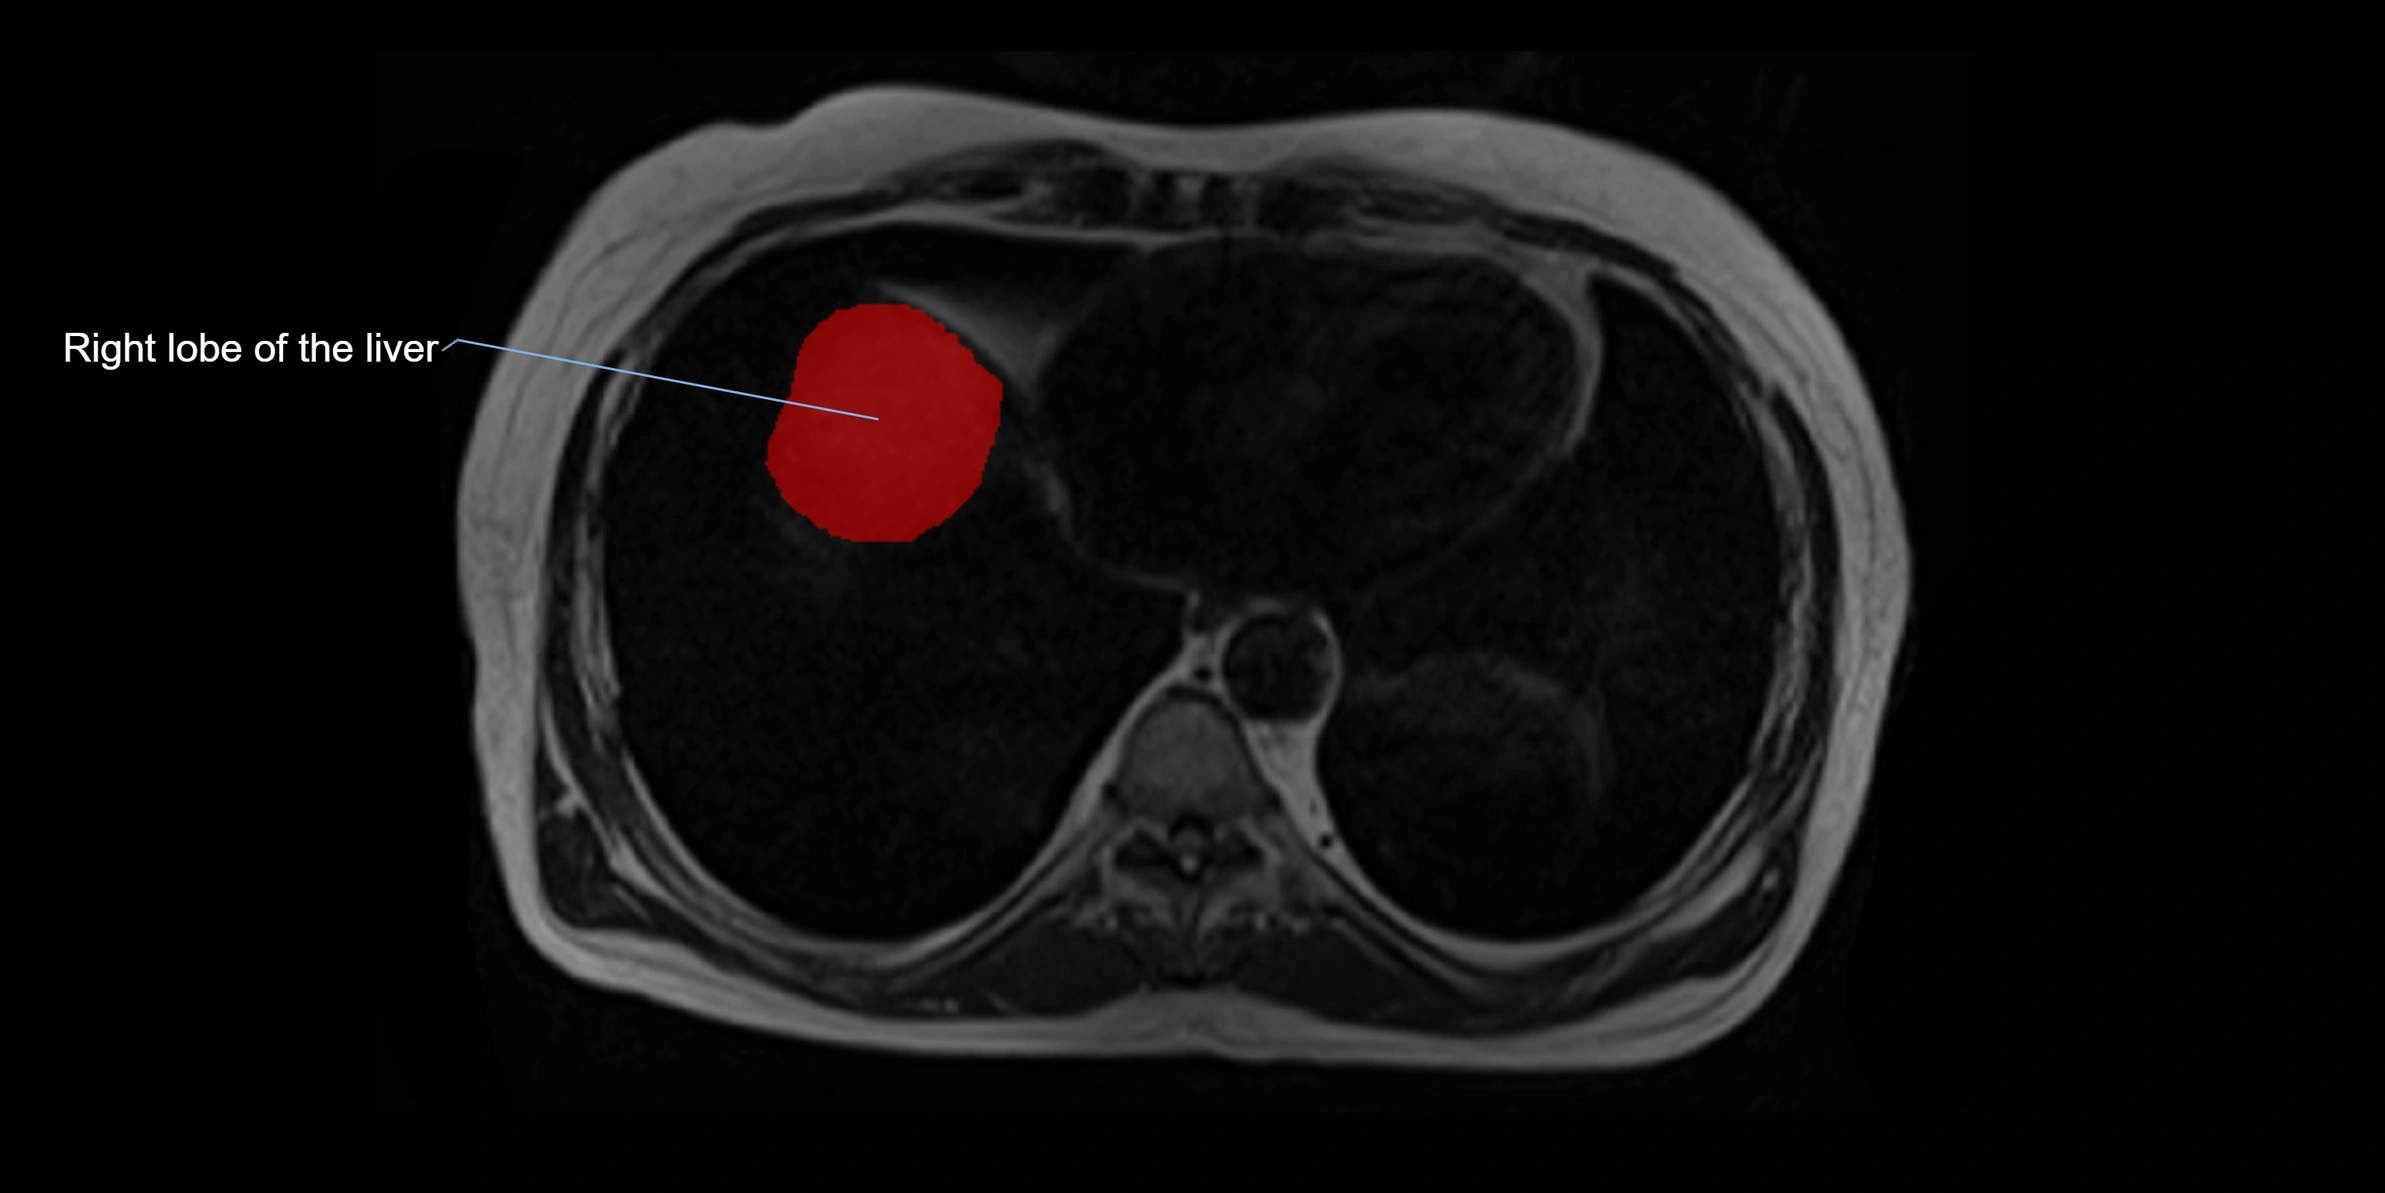

MRI image

image